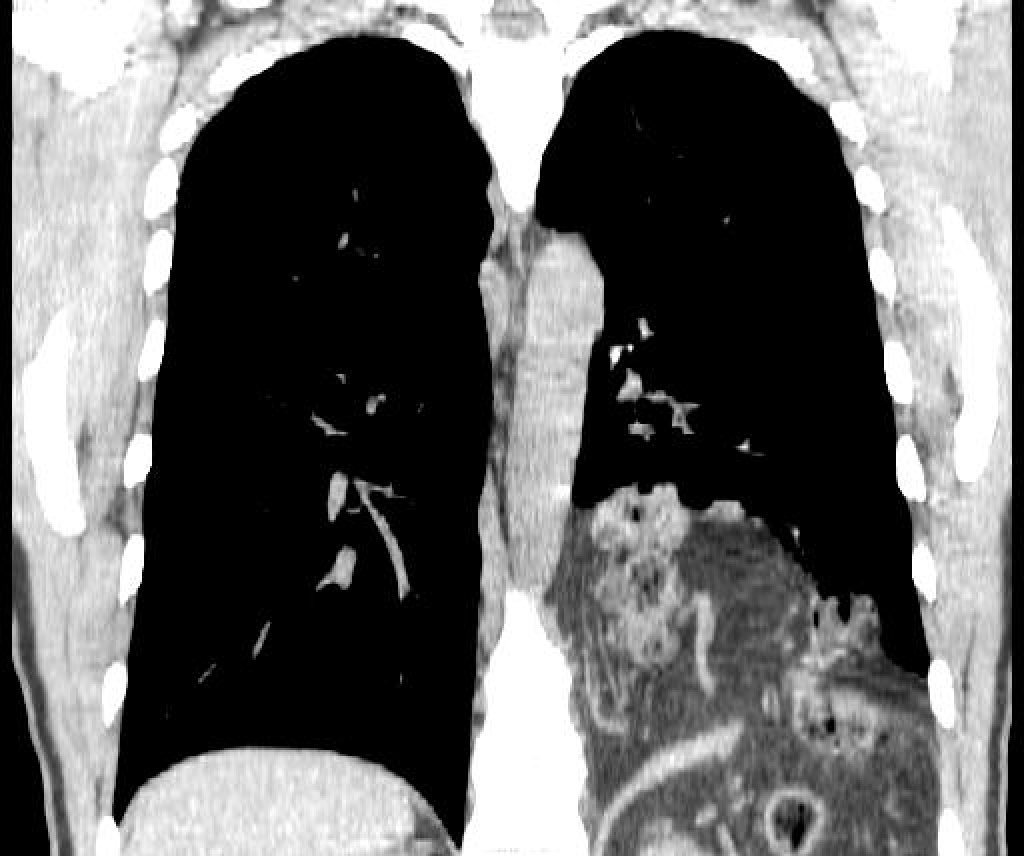

Анатомия диафрагмы и треугольника Бохдалека

Раздел: Визуальный дайджест